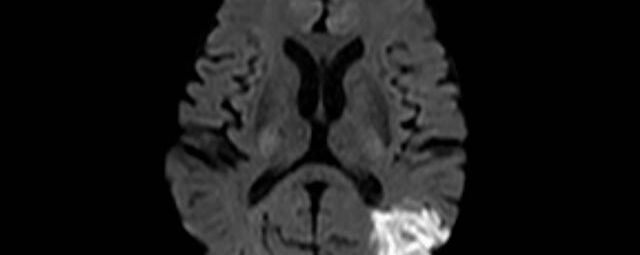

Kopf/Hals

• akute Schlaganfalldiagnostik und chronische Durchblutungsstörungen

• entzündliche Prozesse des Gehirns oder der Gesichtsweichteile

• Tumore

• Abklärung Schwindel, zentrale Sehstörung, Kopfschmerz

• Metastasenverdacht

• Multiple Sklerose

• Abklärung Hirnnerven, Schädelbasis inkl. Hypophyse

• Abklärung Kleinhirn, Hirnstamm, Halsmark

• intrakranielle Gefäße (Abklärung Verschluss, Stenose, Aneurysma)

• Halsgefäße zur Therapieplanung (z.B. Stent, Operation)